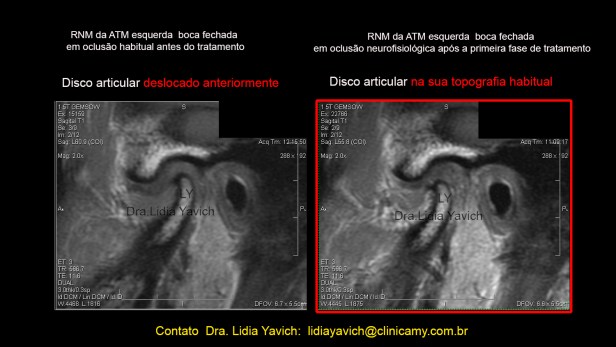

RNM: Ressonância Nuclear Magnética do paciente. Corte selecionado.

1 corte sagital da ATM ESQUERDA em boca fechada antes do tratamento. Deslocamento redutivel do disco articular.

2 -A mesma imagem com realce de cores.

3 -corte sagital da ATM ESQUERDA em boca aberta antes do tratamento.

4– A mesma imagem com realce de cores.  RNM: Ressonância Nuclear Magnética do paciente. Corte selecionado. Corte sagital da ATM DIREITA em boca fechada antes do tratamento.

Corte sagital externo da ATM esquerda em boca fechada antes do tratamento mostrando o DESLOCAMENTO DO DISCO ARTICULAR e a RECAPTURA DO DISCO ARTICULAR após o tratamento.

Controle comparativo da segunda ressonância nuclear magnética após a primeira fase do tratamento. Serão postadas as imagens da ATM esquerda, que apresentava o deslocamento do disco articular.

A ATM do lado direito não apresentava deslocamento, só as diferencias estruturais entre as duas cabeças mandibulares.

Corte sagital externo da ATM esquerda em boca fechada antes do tratamento mostrando o DESLOCAMENTO DO DISCO ARTICULAR e a RECAPTURA DO DISCO ARTICULAR após o tratamento.